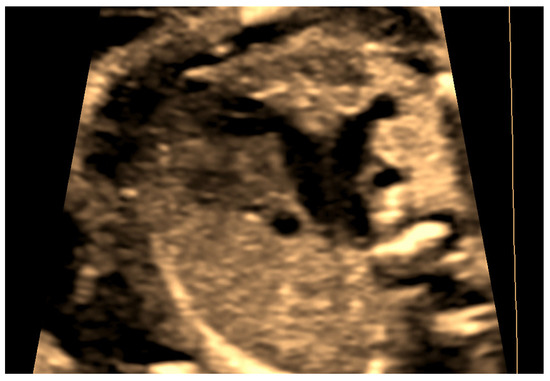

4.2. Case 2